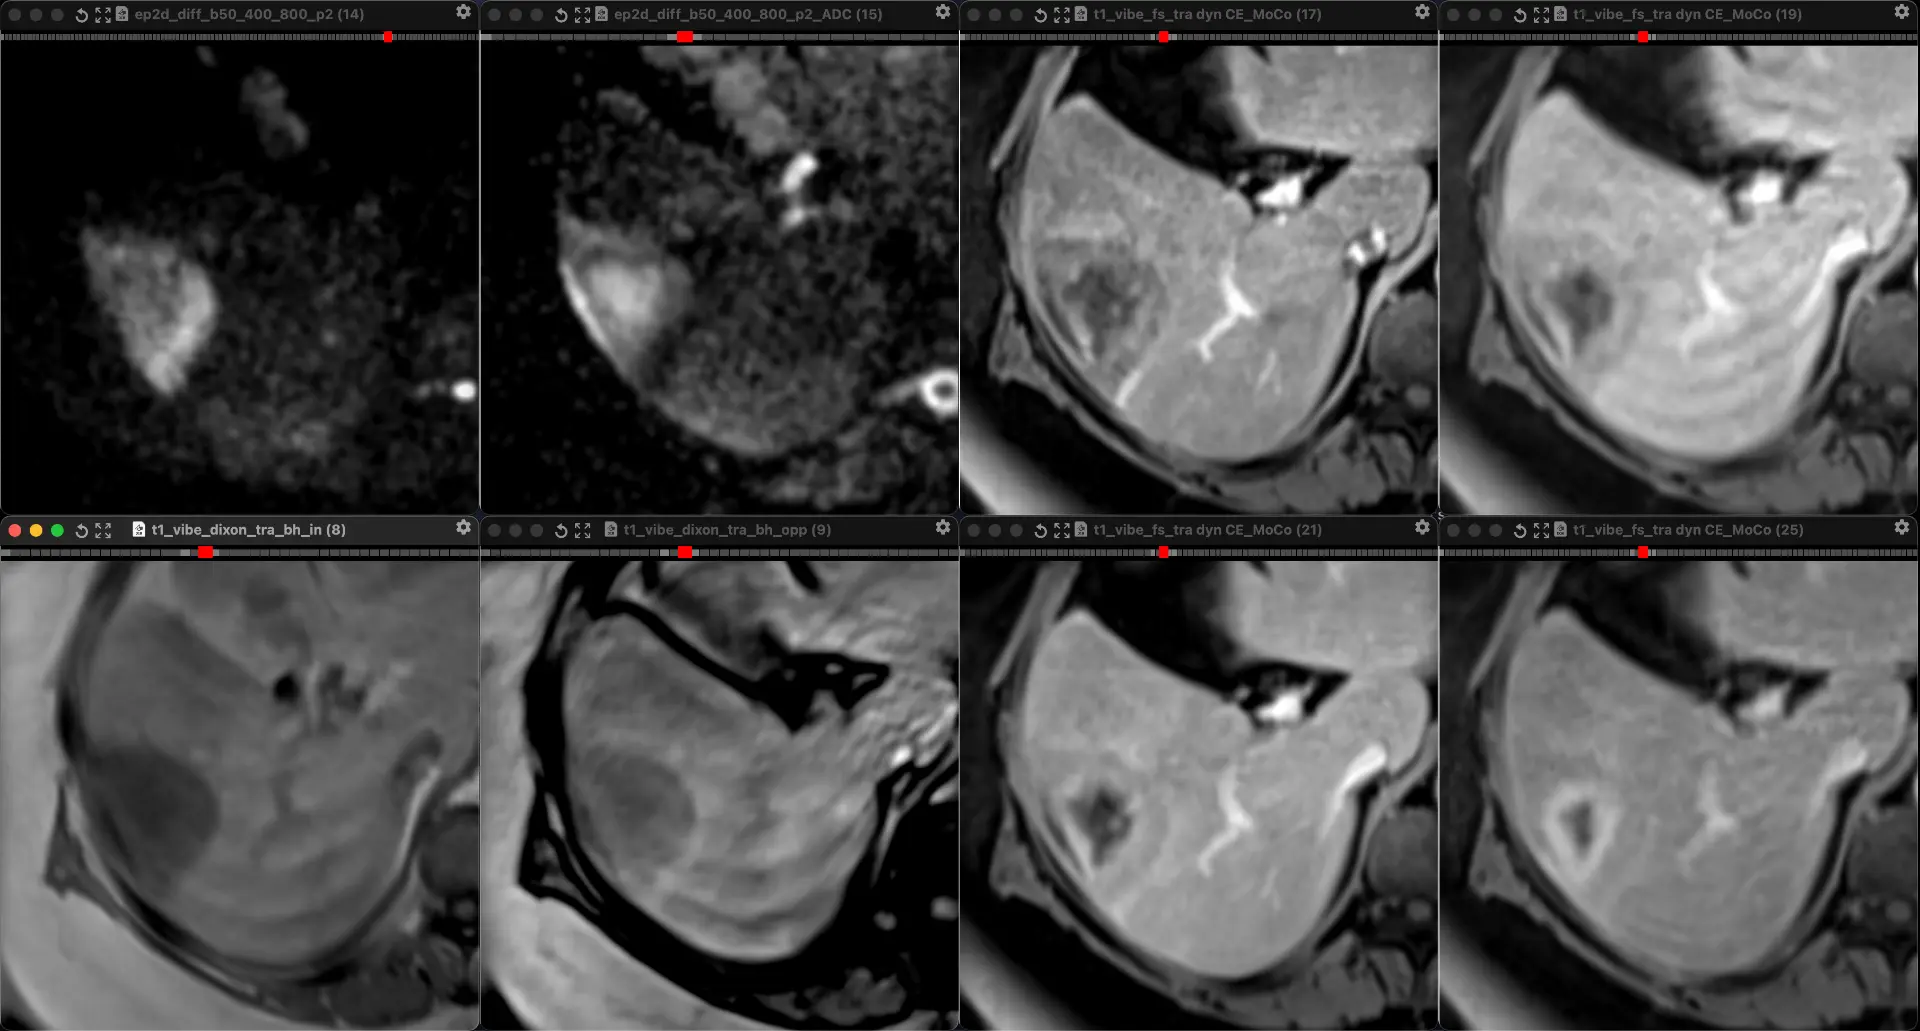

ЖЕНЩИНА 38 лет, фокальное изменение печени выявлено на УЗИ.

Повторные #КТ (с разницей в 2,5 месяца) без динамики. Имеется медленное, постепенное, слабоинтенсивное накопление контраста от периферии к центру.

На #МРТ - очень высокий сигнал на Т2, низкий на Т1, «лучистые» контуры. Истинное ограничение диффузии (ADC=460±109х10-6 кв.мм/с). Накопление контраста такое же, но на МРТ лучше видны краевое узелков накопление в артериальную фазу, тотального контрастирования нет даже на отсроченной фазе (через 5 минут).

Картина характерна: это гиалинизированная/ #склерозированнаягемангиома. Характерное стяжение контура является свидетельством склерозирования: уменьшения объёма, «рубцевания».

Гемангиомы с суженными кавернозными пространствами из-за склероза имеют большее количество более толстых и неровных перегородок, которые могут препятствовать диффузии молекул, что приводит к снижению значений ADC.

Склерозированные гемангиомы печени — это редкие доброкачественные поражения, которые часто трудно отличить от злокачественных, ибо они не имеют типичных для кавернозных гемангиом признаков.

Но! Часть признаков все равно сохраняются:

1. Значительный гиперсигнал на т2

2. Резкие, хоть и неровные, контуры

3. Центрипетальное, и иногда с приставочными узелками накопления контраста на артериальной фазе, контрастирование, пусть и неполное.

4. Стабильность в динамике